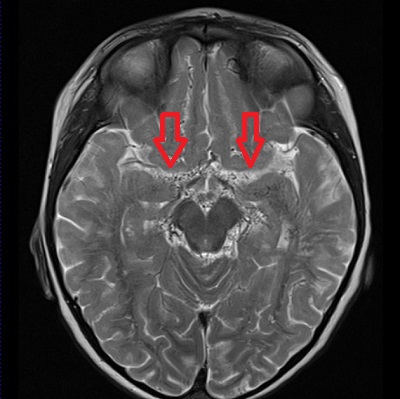

- 類もやもや病(ウィリス動脈輪閉塞症)

特に原因のはっきりしない「もやもや病(ウィリス動脈輪閉塞症)」は、内頸動脈末端と前中大脳動脈部が狭窄・ 閉塞し、基底角部の異常血管網(もやもや血管)が発達する謎の病気です。

甲状腺機能亢進症/バセドウ病など基礎疾患がある場合、「類もやもや病」と言われ、甲状腺治療開始後に脳虚血症状も改善する報告が多くあります。状況によっては(改善が見込めない場合)、甲状腺機能改善後に脳神経外科で脳血行再建術を行う事になります。